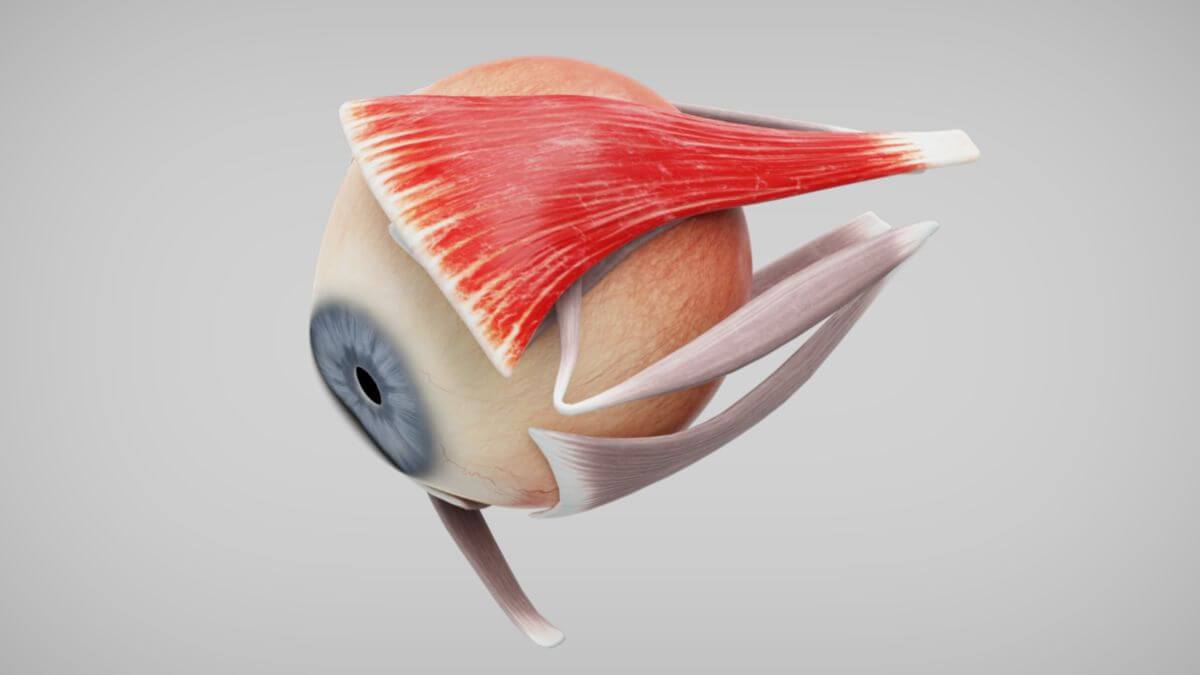

Die Muskeln

Im Bereich um das Auge herum gibt es eine Vielzahl von Muskeln. Das sind zum einen die Muskeln, die für die Bewegung des Auges selbst verantwortlich sind. Auf der anderen Seite gibt es mehrere Muskeln, die für die Mimik verantwortlich sind.

Der Muskulus levator palpebrae superioris gehört zu den äußeren Augenmuskeln und verläuft oberhalb des Musculus rectus superior (https://flexikon.doccheck.com/de/Musculus_levator_palpebrae_superioris). Das Anspannen des Musculus rectus superior sorgt dafür, dass das Auge nach oben gedreht wird (https://flexikon.doccheck.com/de/Musculus_rectus_superior). Der Muskulus levator palpebrae superioris ist veräntwortlich für das heben des obenren Augenlids und somit das Öffnen des Auges. Er wird außerdem agonistisch, also gleichzeitig, mit dem MRS angespannt und sorgt dafür, dass das Augenlid beim Nach-Oben-Schauen angehoben wird und somit die Pupillen nicht verdeckt (TODO: das nicht verdecken ist bisher frei erfunden, QUELLE).

Musculus rectus superior:

Musculus rectus superior: